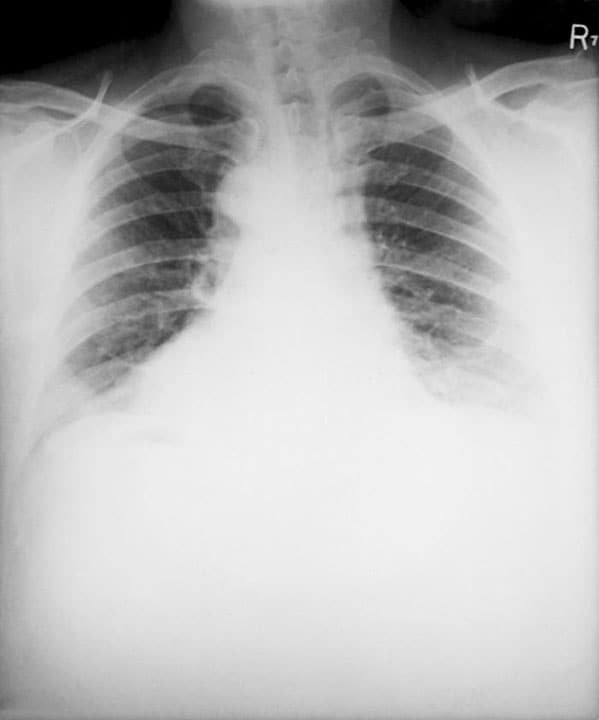

Inhalation anthrax happens when a person breathes in anthrax spores. It's the deadliest form of the disease. People who work in places such as wool mills, slaughterhouses, and tanneries may breathe in the spores when working with infected animals or contaminated animal products. Inhalation anthrax starts primarily in the lymph nodes in the chest before spreading throughout the rest of the body.

Inhalation anthrax

Symptoms include:

- Fever and chills

- Heavy sweats

- Chest pain, cough, or shortness of breath

- Confusion or dizziness

- Nausea, vomiting, or stomach pains

- Headache or body aches

- Extreme tiredness